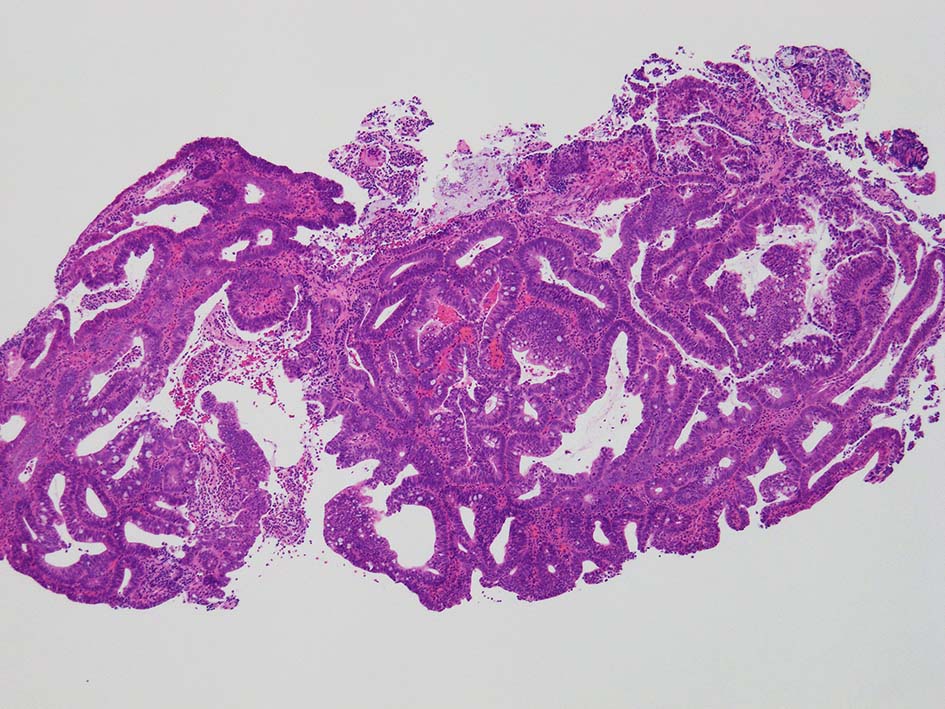

膀胱鏡検査で頸部6時方向に乳頭状腫瘤があり, 膀胱がん疑いで生検をおこなう.

腸管型の腺癌。大腸の高分化腺癌と組織学的に区別は難しい.

GI tract, とくに大腸癌の膀胱浸潤/転移を最初に考えた.